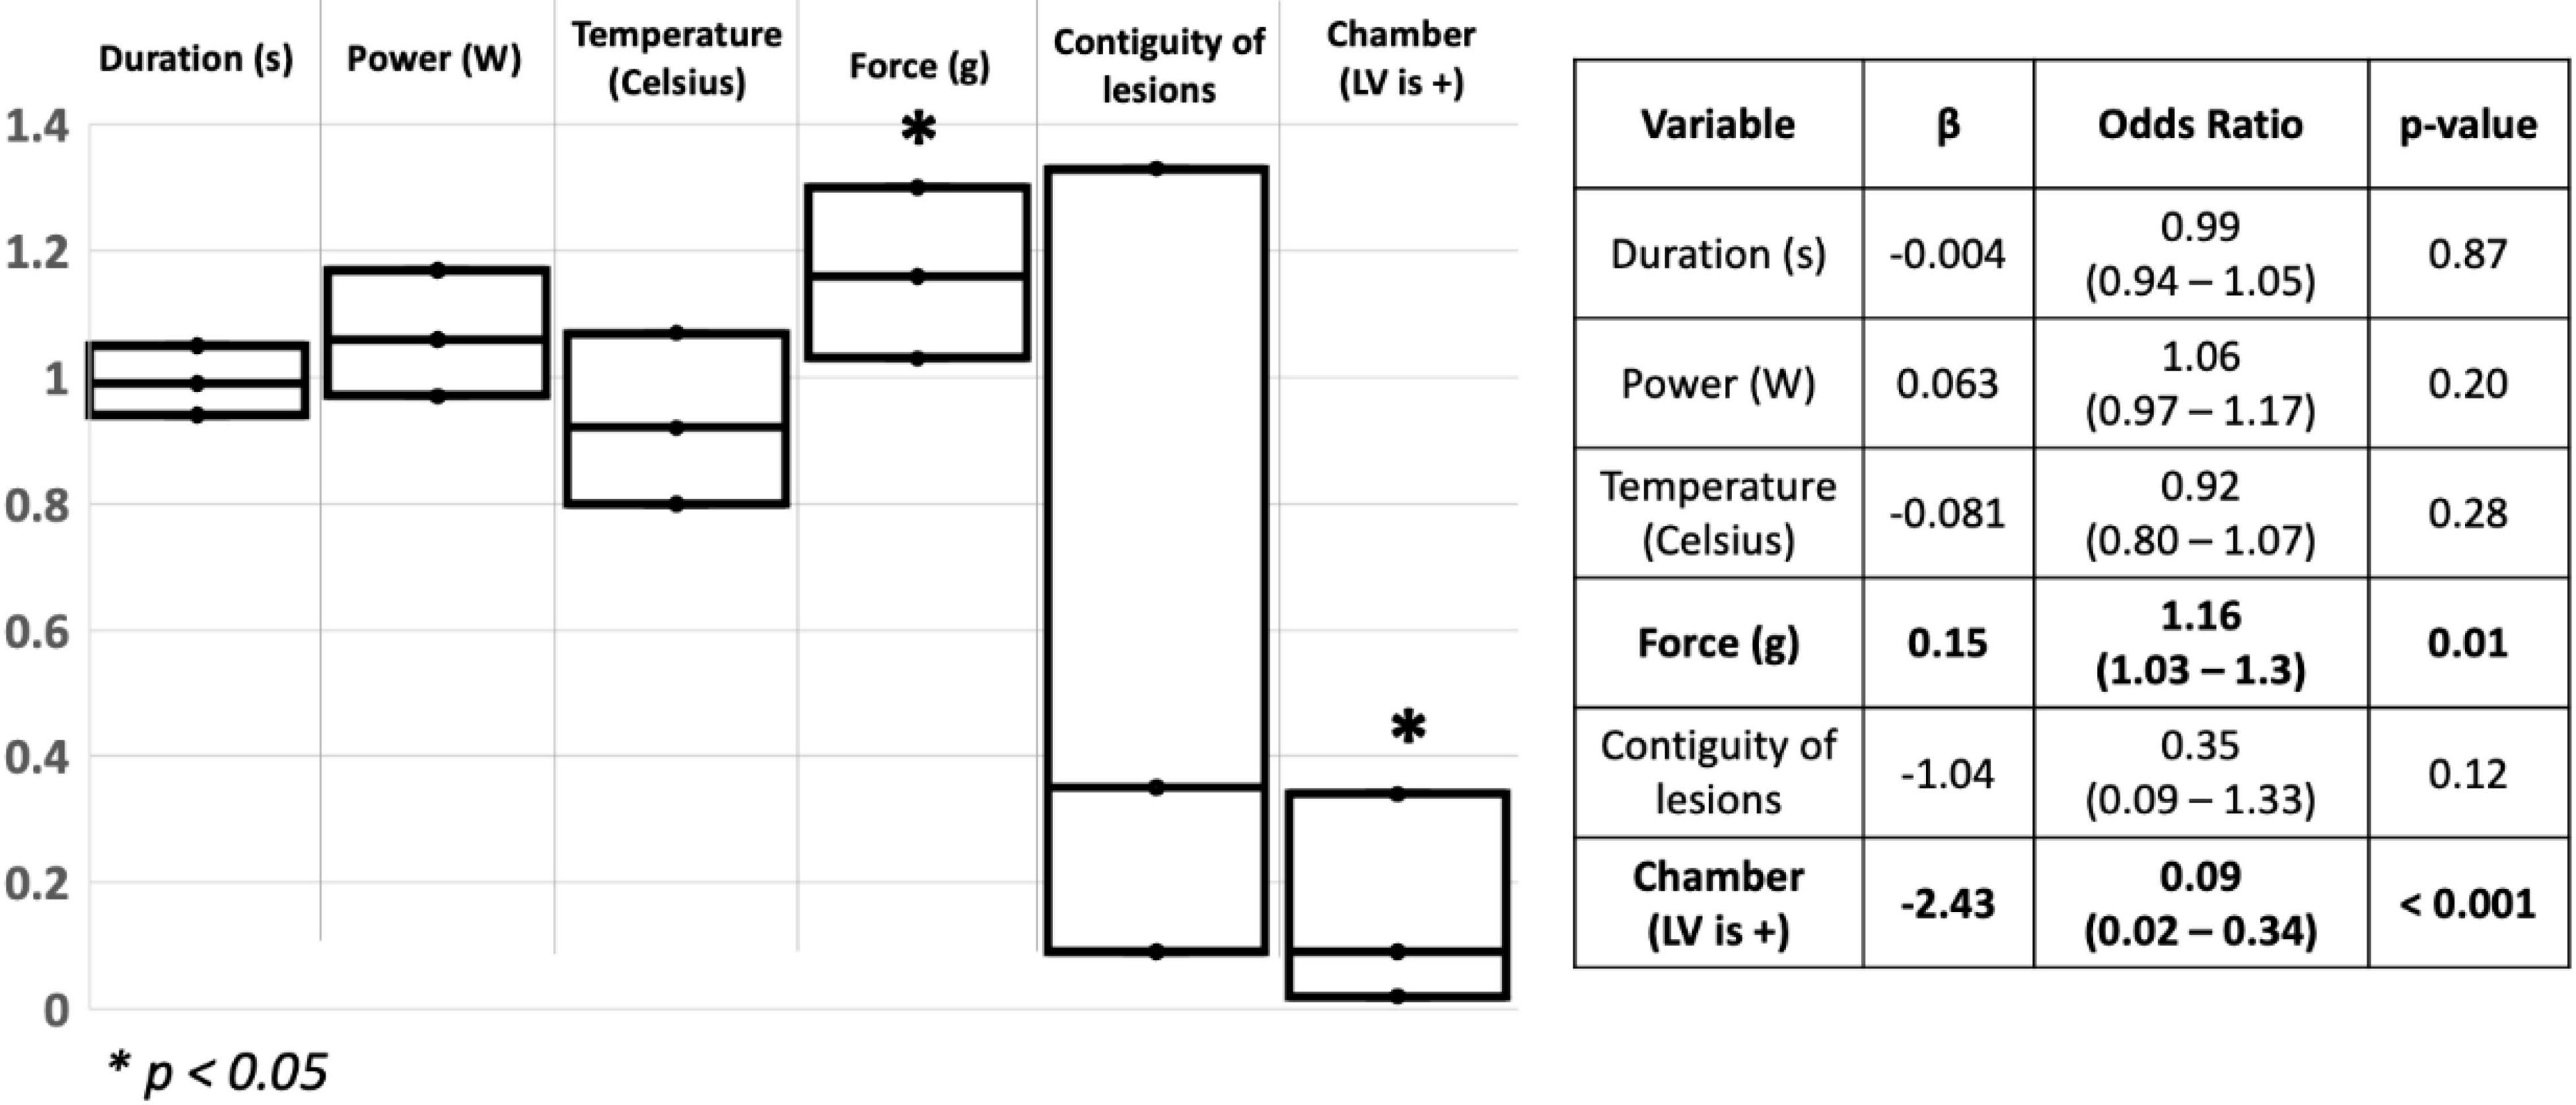

Out of the 81 lesions created, we delivered 33 ablation lesions in the LV and 48 in the RV. Of the lesions delivered in the LV, 4 were transmural while 23 were transmural in the RV. We found that higher CF was a significant predictor of transmural lesion formation (β = 0.15, OR = 1.16, 95% CI [1.03 – 1.3], p = 0.01), and lesions delivered in the RV were more frequently transmural than lesions delivered in the LV (β = −2.43, OR = 0.09, 95%CI [0.02 – 0.34], p < 0.001) (Model fit: Chi-Square = 26.75, p < 0.001). Other ablation parameters were not significant predictors of transmural lesions in our cohort. Results of the logistic regression are shown in Figure 2.

Figure 2. Schematic representation of the logistic regression used to assess for predictors of transmurality in the ventricles. S: Seconds; W: watts; g: Gram; LV: Left ventricle. *p < 0.05.